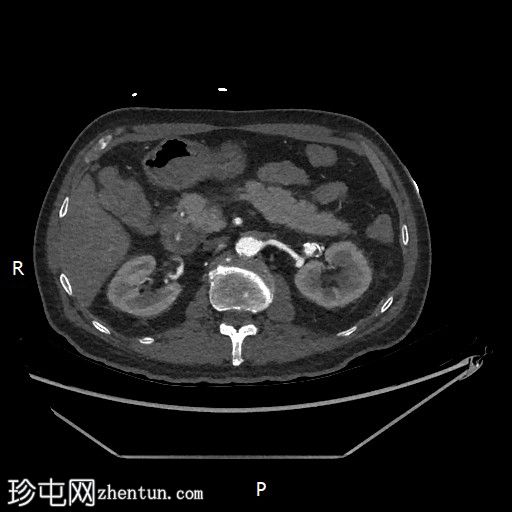

轴位增强扫描

动脉期

门静脉期

胃内出血

造影剂外渗提示十二指肠第二段活动性出血